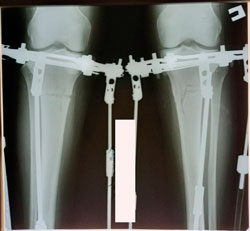

Исходник - 36 лет.

Дата операции - 02.12.2020

Ещё раз: невозможно устранить варусную деформацию при помощи круропластики

Очередной пример!